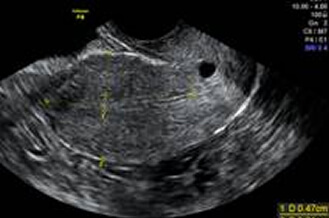

子宮肌瘤